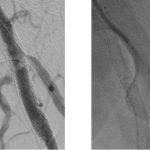

endovascular-therapy-for-restenosis-of-a-stent-placed-over-the-femoral-bifurcation